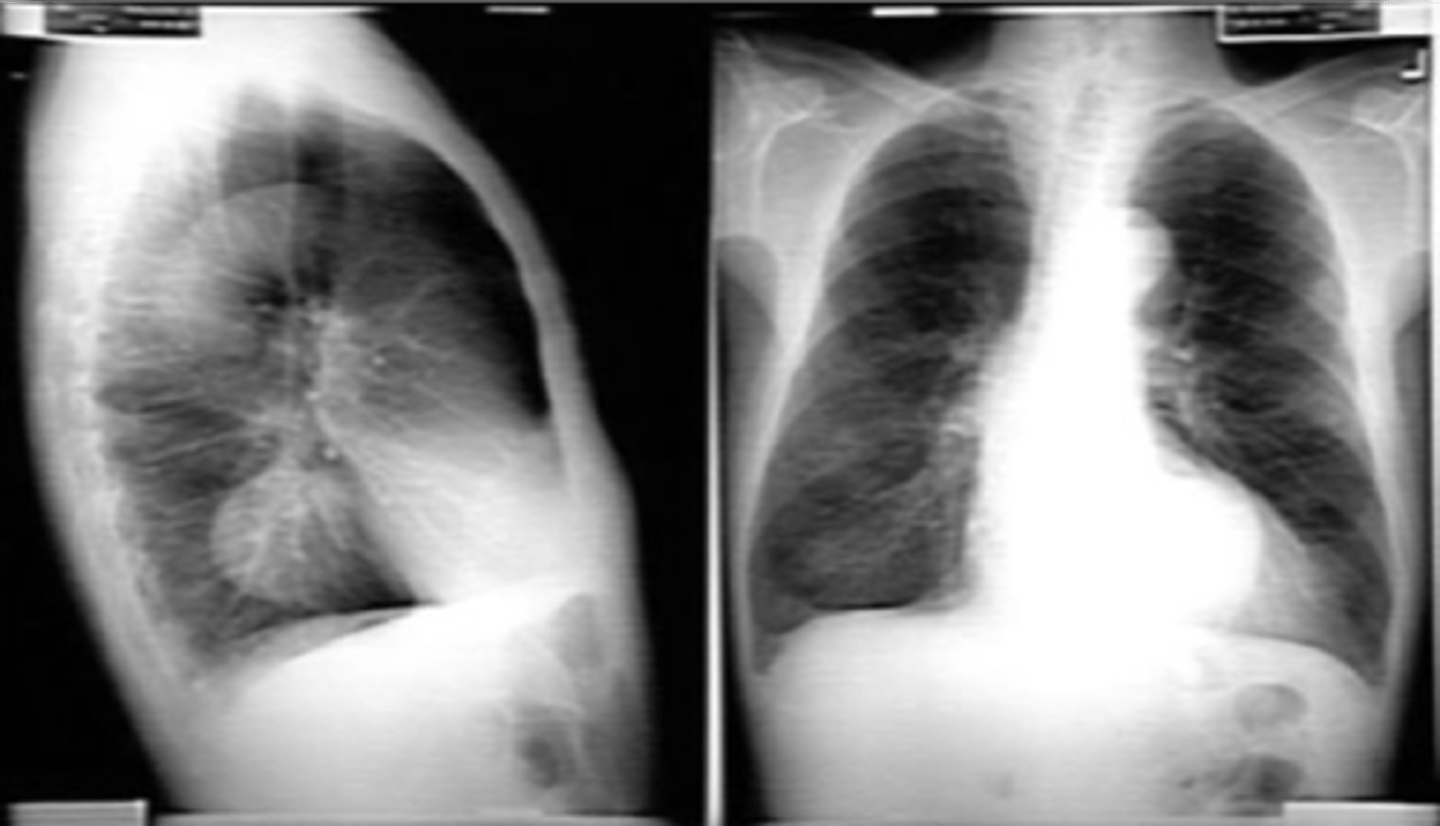

Right sided atelectasis

Right sided non tension pneumothorax

Atelectasis (right)